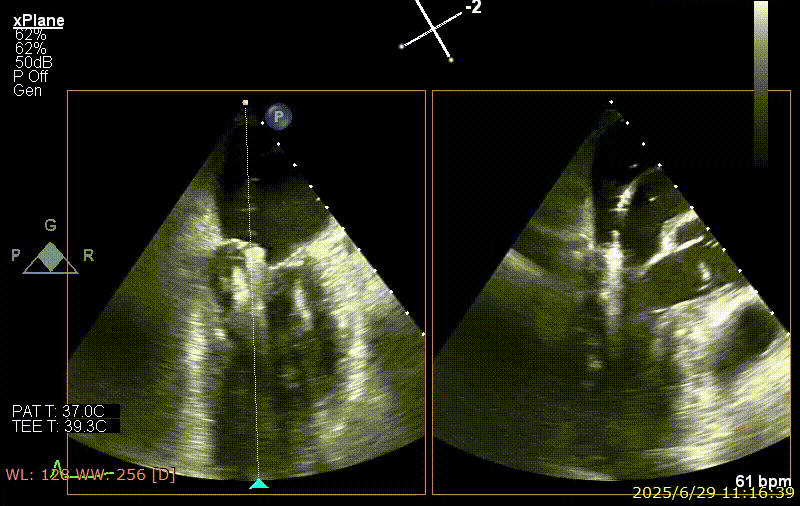

手术步骤

器械植入后二尖瓣 AP 径约 35 mm,CC 径约 39 mm;夹合器固定好、组织桥稳定,前瓣夹闭后瓣叶长度 25 mm,后瓣夹闭后瓣叶长度 7 mm;二尖瓣开放好,瓣口呈大小双孔,二尖瓣瓣口面积约 2.8 cm²,平均压差 1 mmHg,关闭可,二尖瓣反流明显减轻(从术前反流 4+显著改善至 1+),手术全程无需体外循环支持,无需输血,无需射线全超声引导。患者术后第二日回普通病房,患者恢复良好,术后第五日即出院。